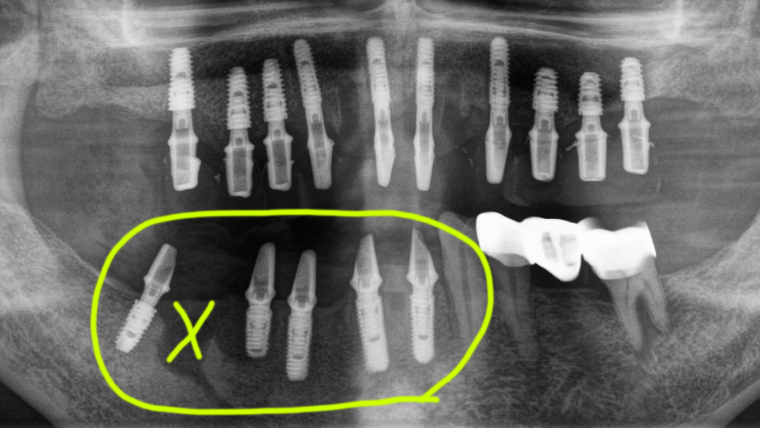

염증이 심한 5번 치아부위에는 임플란트를 심지 않았고 4번은 뼈가 많이 파괴된 것처럼 보이지만 바깥쪽 뼈만 약간 무너져 있어서 혀쪽에 남아있는 뼈에 식립을 해서 전체적으로 뼈이식을 필요하지 않았습니다.

이렇게 식립을 했고 여기에도 수술당일 임시치아를 만들어 드렸어요. 하지만 이런 경우에는 위에 치아와 살짝 닿지 않게 교합을 형성해야 합니다.